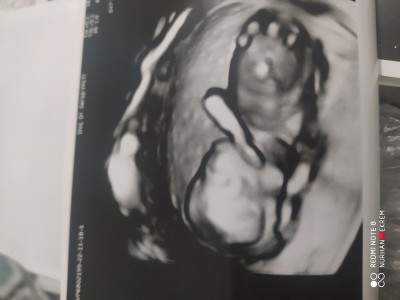

Merhaba arkadaşlar önceliğim sağlık tâbi ama 7 yıldan sonra olunca İster istemez merak ediyorum acaba tahmin ede bilir misiniz doktor söylemedi iki hafta sonra gel dedi:)

Gebelik haftası 13+2